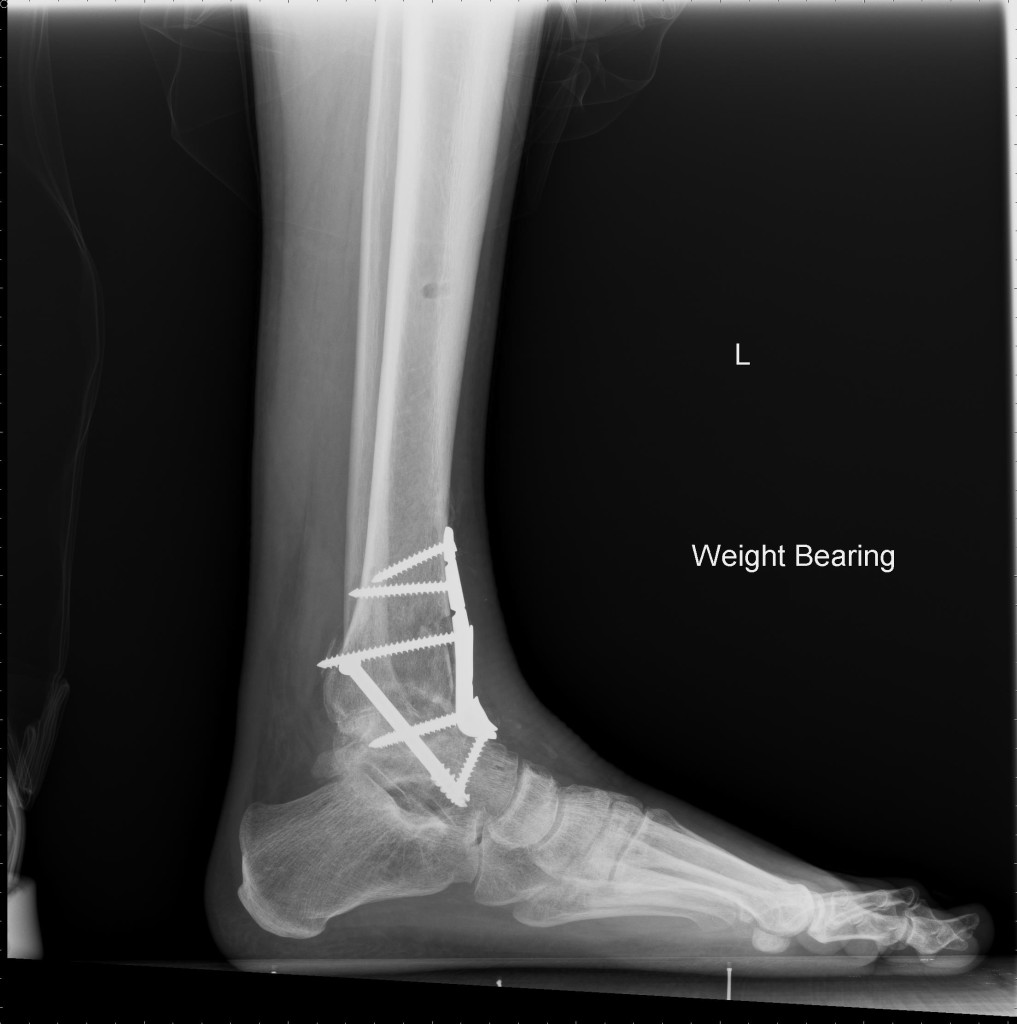

The unknown was scary. I was 32 and all I knew was that I was losing the functionality of my ankle for the rest of my life. But Martin was not just my doctor; he was my partner and coach through the process. I often questioned if I would be able to walk pain free or live an active healthy lifestyle again. He always assured me that I would one day be able to put the pain of the past behind me. Though I cannot physically run (thank you six screws and a metal plate), I have taken up the sport of road cycling in a whole new manner. Last season I rode over 1,400 miles with a goal this year to approach 2,000 miles.